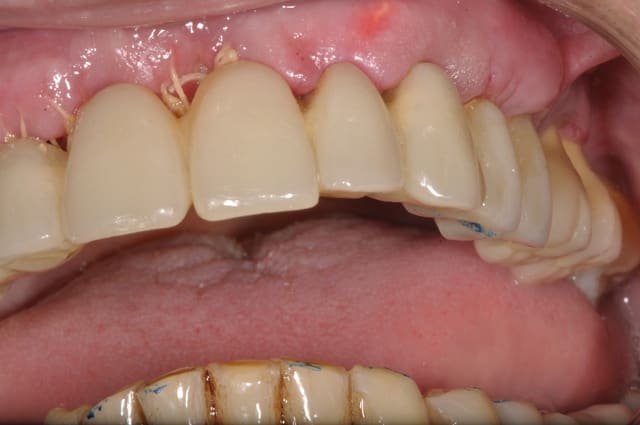

les contrôles à 7 jours, 2 photos par cas

amusez vous à les reconnaitre!

Comme cette technique semble vous passionner, je mets un cas en photos:-))

Pour 3000€ de plus je posais un optragate! C'est le patient qui n'a pas voulu!!!!!!!!!!!!!!!!!!!

Ton avis sur le résultat cicatriciel à 7 jours de ce plan de traitement ?